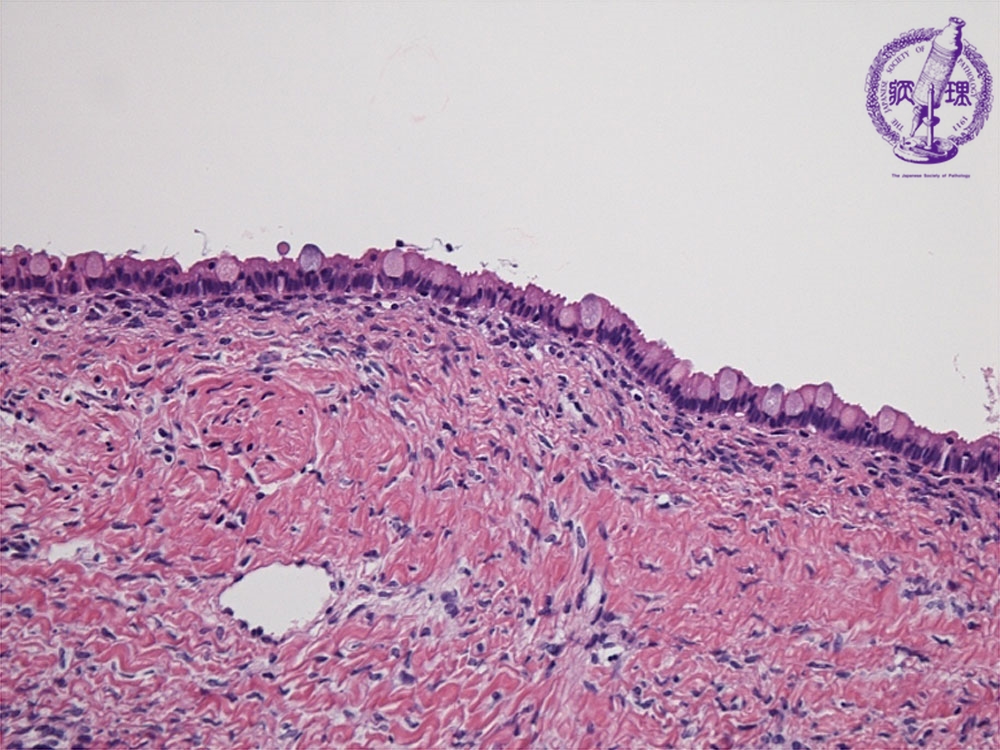

- (7)Mucinous cystadenoma

Histology (HE stain, high power): Single layer of columnar cells (yellow dotted line) in inner surface of cyst. The cells with clear cytoplasm and the nuclei are located at the side of basement membrane.